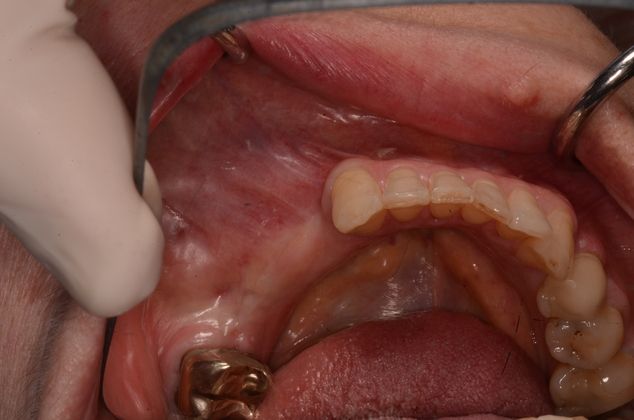

Three missing lower teeth replaced with implants and screw retained crowns.